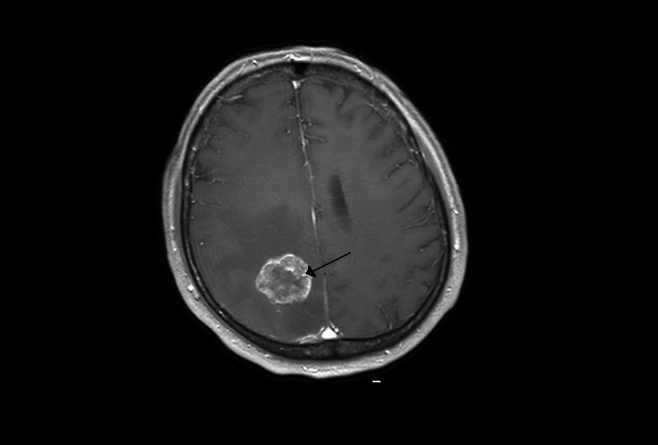

그러나 문제의 원인은 심리적인 것이 아닌 생물학적인 원인이었다. CT 검사를 받은 결과 그의 뇌에서는 7.5×8.1cm 크기의 종양이 발견됐다. 의료진은 그에게 3개월밖에 남지 않았을 수 있다며 시한부 진단을 내렸다.

앤디는 종양의 95%를 제거하는 수술을 받고 6주간 방사선 치료와 항암 화학요법을 병행했다. 수술 직후에는 얼굴 경련, 신장 감염 등 부작용이 있었고 뇌 손상으로 감정을 제대로 표현하지 못하는 어려움도 겪었다.